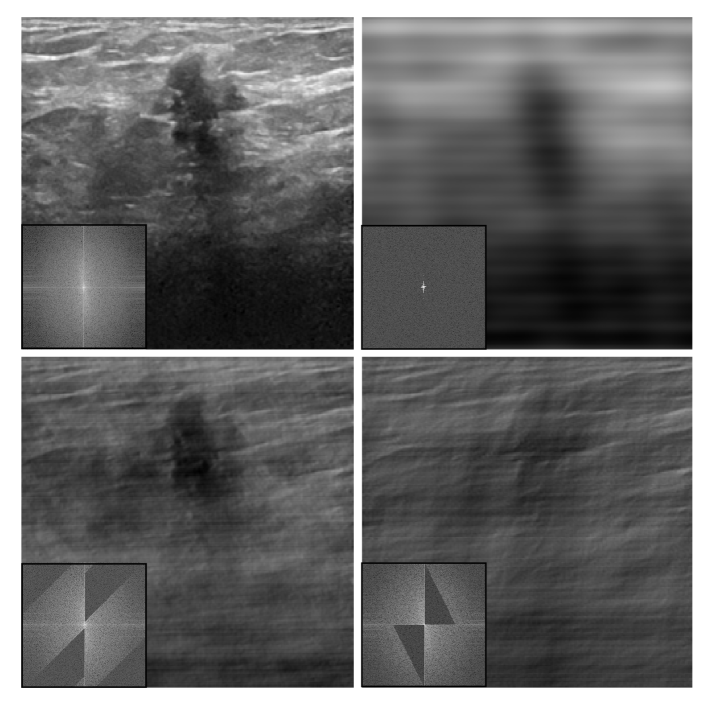

where is the trained weight matrix (non-negative). For the Linear log and the General log configurations, only the log transforms of the spectra were computed. These configurations are designed to ‘boost’ the appearance of the smallest frequency pixel values in the spectrum, where the intensity of a typical central frequency oftentimes ‘overwhelms’ the smaller values on the periphery (see insets in Fig. 2 below to see typical spike-shaped learnt spectra).

We look for a global filter that will leave only those frequencies that improve the prediction of the base model. A high-pass filter, in which high frequencies are passed and low frequencies are suppressed, enhances edges. While visualizing details with a low-pass filter reduces outliers and contrast, i.e., yielding a smoothing effect. For each task, one needs a specific filter, which is not easy to select manually (Fig. 9). Therefore, we can delegate the task of filter selection to the computer by integrating the appropriate adaptive neural layer for global frequency filtering, which will be trained alongside the main model.